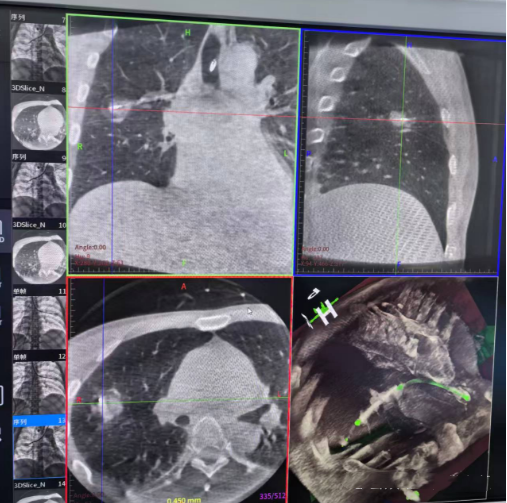

Lungpro全肺导航系统术前规划

1. Lungpro全肺导航系统:犹如为医生安装了“GPS肺内导航仪”,它能基于患者CT数据重建精细的支气管树3D地图,规划抵达肺外周“隐秘角落”结节的最优路径,避开重要血管,极大提升操作精准度。